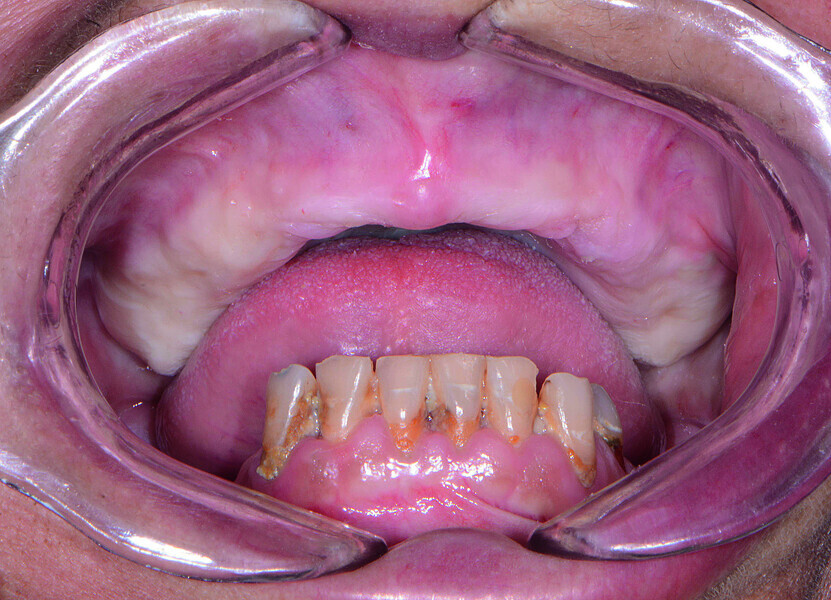

Fig. 2: Pre-op retracted view without denture.